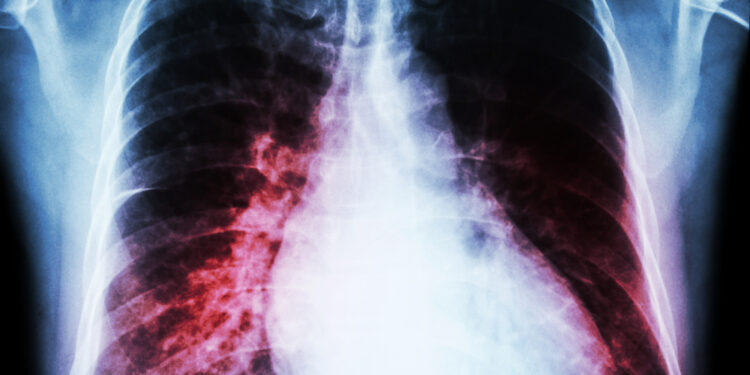

Kaip nustatoma kardiomegalija?

Diagnozė prasideda nuo simptomų, šeimos ligų istorijos bei gyvenimo būdo pokalbio. Gydytojas gali pastebėti širdies ūžesį klausydamas krūtinės stetoskopu. Priklausomai nuo širdies funkcijos, būdingi ir papildomi požymiai: galūnių tinimas, skysčių kaupimasis plaučiuose ar išbrinkusios kaklo venos.

Tiriant gali būti atliekami šie tyrimai:

- Krūtinės ląstos rentgenograma – širdies ir krūtinės vaizdas